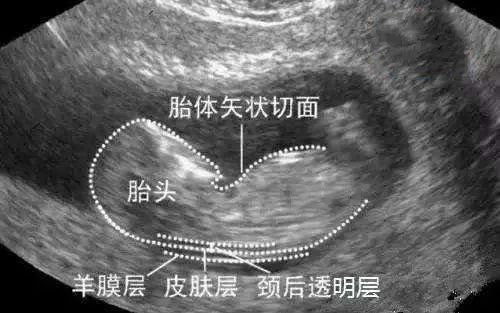

1.NT-胎儿颈项透明层厚度

NT检查是唐氏筛查的一种,又叫颈项透明层检查,俗称为“早唐筛查”,用于评估胎儿是否有可能患有染色体异常和心脏问题,通常在孕11-13周+6天进行。

● 妊娠11周,NT厚度应≦2mm;

● 妊娠13周+6天,NT厚度应≦2.7mm;

● 当NT厚度≧6.5mm时,染色体异常的发生率为65%;

● 如果彩超提示NT厚度≧2-3mm时,一定要看产科医生、优生遗传科医生,帮助您了解背后可能存在的风险。